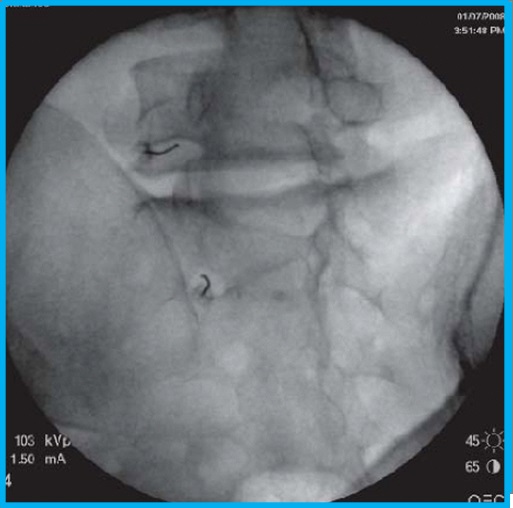

Η διατρηματική επισκληρίδιος έγχυση αποτελεί μια πιο εξειδικευμένη ιατρική πράξη, η οποία εφαρμόζεται κάτω από ακτινοσκοπικό έλεγχο και με χρήση σκιαγραφικής ουσίας για την απεικόνιση του νεύρου, όπου μικρή ποσότητα τοπικού αναισθητικού και κορτιζόνης εγχέεται απευθείας στο νευρικό τρήμα που αποτελεί το σημείο εξόδου του νεύρου από την σπονδυλική στήλη.